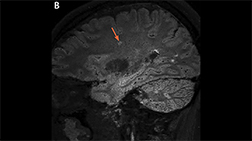

The central vein sign on fluid‑attenuating inversion recovery* (FLAIR*) MRI.

The central vein sign on fluid‑attenuating inversion recovery* (FLAIR*) MRI.

A sagittal 3T FLAIR* brain MRI shows multiple lesions with the central vein sign (orange arrows), appearing as hypointense dots or lines, located centrally within the lesion, depending on the blood vessel orientation. The FLAIR* technique was developed by Daniel S. Reich, MD, PhD and colleagues as described in Sati P, et al. Radiology. 2012;265(3):926-932. Image contributed by Daniel S. Reich, MD, PhD.